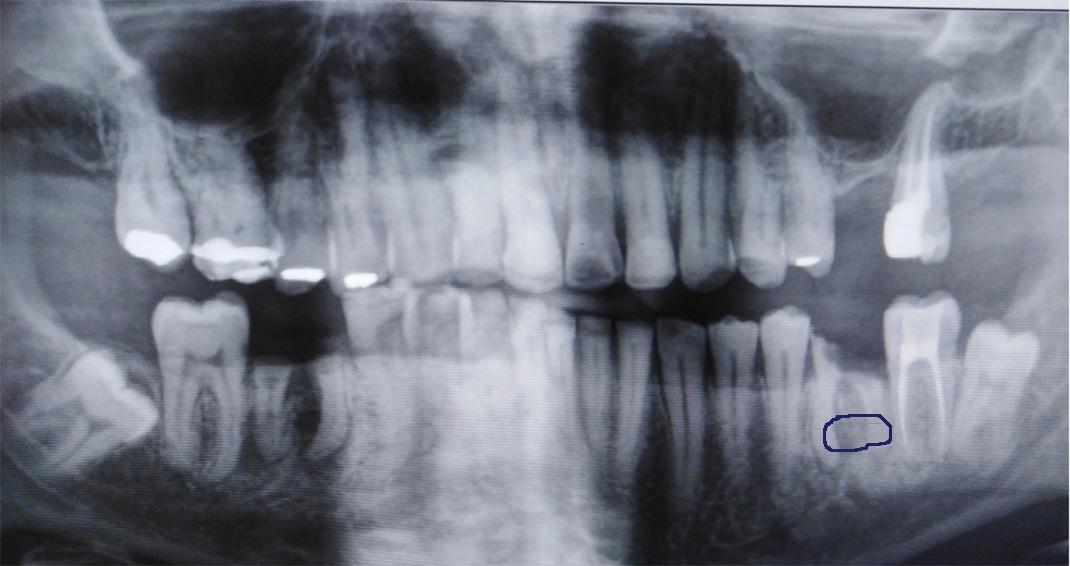

Dit was de foto die de tandarts padrao op 07-10-2021 ter beschiking had

Er is geen nieuwe foto tenminste geen begin foto gemaakt Element 36 is niet meer te behouden Deze foto is pas gemaakt nadat hij element 36 had weg gefreest en 37 was al geopend voor een wortel kanaal behandeling

Er zijn op de fotos ookop element 36 en 37 geen wortepunt onstekingen te zien

Toen ik zei dat het volgens mijn twee second opinions het de gewoonte was om detail foto te maken . Daarop zei de weledelgeleerde tandarts A Padrao dat hij dat ook had gedaan .Waarop ik zei dat hij dat had gedaan nadat de kies element 36 was weggefreest!!. Ook bij een second opinion zeg de betreffende tandarts:Hij kon er niets over zeggen er was geen beginsituatie . Daar waar het vraagteken staat er is geen beginfoto .